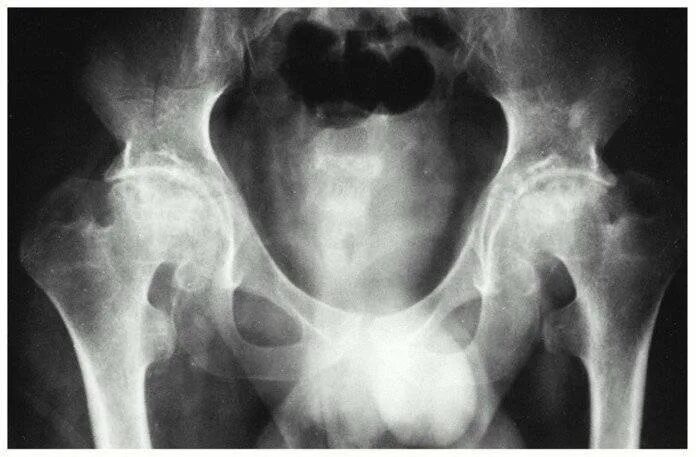

Артрит тазобедренного сустава симптомы